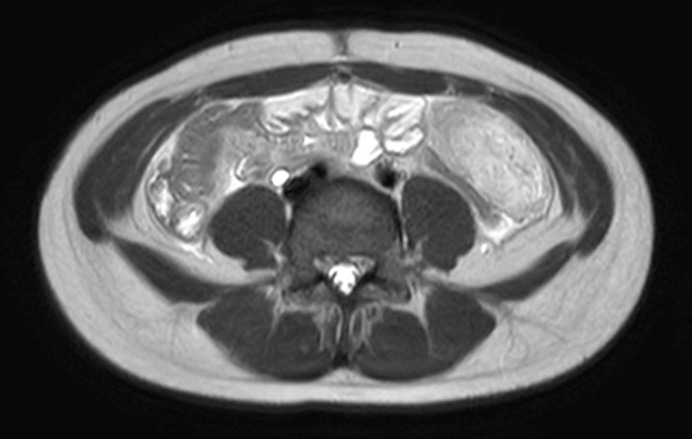

Case presentation: The patient, an 11-year-old girl, complained of dull periumbilical pain and nausea, and radiological examination showed a mass lesion in the abdomino-pelvic cavity. On laparoscopy, a plaque-like, flat mass was seen in the greater omentum, and laparoscopic omental resection was performed. On histopathological examination, the interlobular fibrous septa of omental adipose tissue were widened by inflammatory edema, prominent infiltration of eosinophils, and loose proliferation of myofibroblasts. Dense lymphocytic infiltration was also noted around small veins. Inflammatory changes were mild in the fat lobules, and fat necrosis and infiltration of lipid-laden macrophages were absent. Findings of obliterative phlebitis or arteritis were not seen.